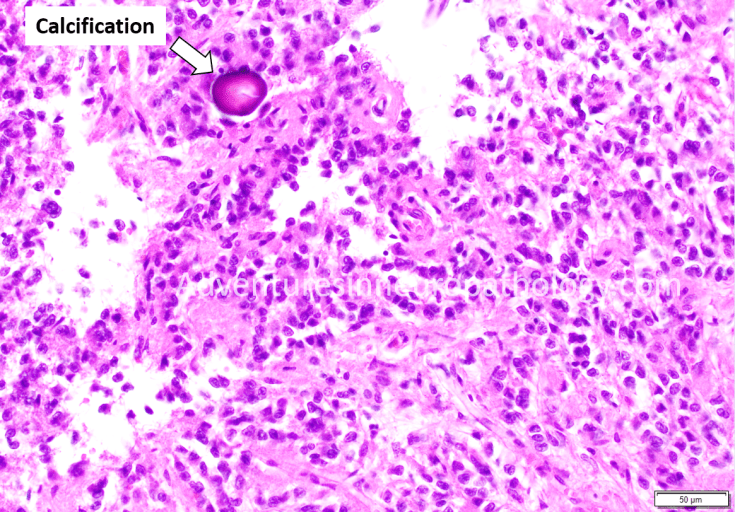

The pineal gland is a midline structure involved in the regulation of circadian rhythm. The “internal clock” that allows for coordination of sleep and wake cycles with changes in night and day is largely regulated by the actions of melatonin, a neurotransmitter that is produced by the constituent cell of the pineal gland: the pinealocyte. Pinealocytes give rise to a rare group of tumors called pineal parenchymal tumors, which includes pineocytoma (grade 1) and pineoblastoma (grade 4). However, normal pinealocytes may be confused for a neoplastic process due to their nuclear features and nested architecture. The pineal gland commonly contains calcifications; in the era prior to MRI and CT scans, these calcifications were instrumental for radiologists’ diagnosis of midline shift because displacement of the midline pineal gland by a brain tumor or trauma could be detected on X ray.